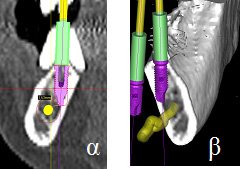

Οι πιο συχνές βλάβες από ερεθισμό στο στόμα είναι τα αντιδραστικά ινώματα (Εικόνες 4 και 5).

Εικόνα 4. α. Ίνωμα της υπερώας από χρόνιο ερεθισμό ολικής οδοντοστοιχίας (βέλος), β. Μετά την χειρουργική του αφαίρεση.